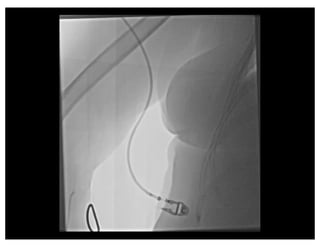

Balloon Assisted Tracking

Patel T, et al CCI 2012

Razor Effect